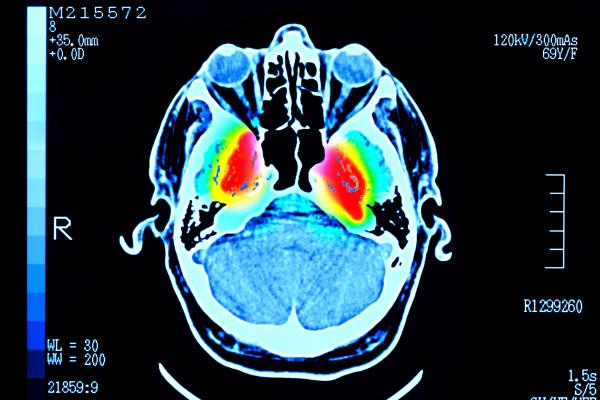

Getty Images மனித மூளை முப்பது வயதின் தொடக்க காலம் வரை இளமைக் கட்டத்தில் (adolescent phase) நீடிக்கிறது. அந்த காலகட்டத்தில்தான் மூளை தனது "உச்ச நிலையை" அடைகிறது என கேம்பிரிட்ஜ் பல்கலைக்கழகத்தின் ஆராய்ச்சியாளர்கள் சுட்டிக்காட்டியுள்ளனர்.

90 வயது வரையிலான சுமார் 4,000 பேரின் மூளை ஸ்கேன் செய்யப்பட்டு, அவர்களின் மூளைச் செல்களுக்கிடையிலான தொடர்புகள் குறித்து ஆய்வு மேற்கொள்ளப்பட்டது.